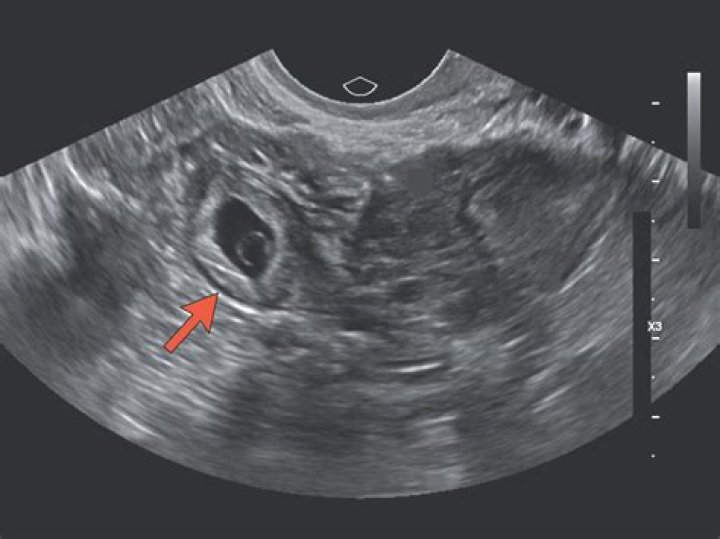

An ectopic pregnancy is usually diagnosed by carrying out a transvaginal ultrasound scan.

An ectopic pregnancy can be suspected if the transvaginal ultrasound examination does not detect an intrauterine gestational sac when the β-hCG level is higher than 1,500 mIU per mL.

Can you see an ectopic pregnancy on ultrasound at 6 weeks?

An intra-uterine pregnancy can usually be seen by 5-6 weeks gestation or when the HCG level is more than 1000 IU/l. In 95% of ectopic pregnancy cases, a good transvaginal ultrasound examination can actually image the ectopic pregnancy in the Fallopian tube.